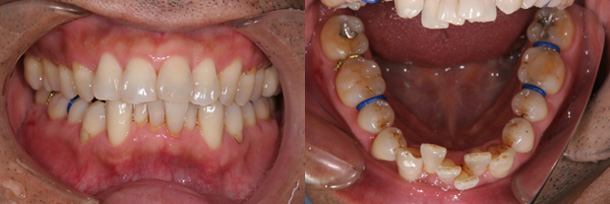

症例:上顎前歯のすき間を改善

主訴:上の前歯のすきっ歯が気になる

診断:上顎の正中離開

年齢:22歳

装置:上顎部分的ブラケット装置

治療期間:5か月

抜歯:なし

費用:100,000円+税

矯正前

矯正中

矯正後